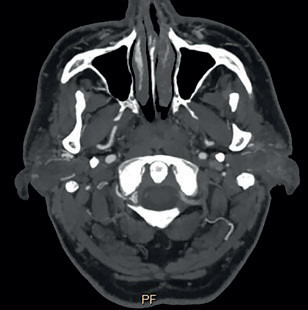

Na zobrazení MR DW (MR obraz s difuzním vážením) byly patrné čerstvé ischemické změny v dolní části levé mozečkové hemisféry v teritoriu PICA (arteria cerebelli inferior posterior) vlevo, a dále v bazi levého brachium pontis. Drobné změny jsou i v teritoriu horní mozečkové tepny vlevo a drobný okrsek restrikce MR DW v dolním okraji pravé mozečkové hemisféry v teritoriu PICA vpravo (obr. 1). Na CTA (výpočetní tomografie – angiografie) a DSA (digitální subtrakční angiografie) byl patrný uzávěr odstupu obou vertebrálních arterií (obr. 2). Zadní mozkové řečiště, tzn. bazilární tepna (BA), PCA a distální části vertebrálních tepen, se plnilo retrográdně cestou zadních komunikant (obr. 3). Retrográdní tok v levé a. vertebralis dosahoval až do extrakraniálního úseku V3 v oblasti oblouku prvního krčního obratle C1 (obr. 4). Nová vyšetřovací modalita QMRA prokázala retrográdní tok v levé zadní komunikantě 30 ml/min a sotva detekovatelný retrográdní tok v bazilární arterii 17 ml/min (obr. 5).

Na kontrolním vyšetření CTA je patrný bypass z povodí arteria carotis externa cestou a. occipitalis na vertebrální arterii (obr. 8A–B). Pooperační vyšetření QMRA ukazuje obnovený antegrádní tok v levé a. vertebralis 60 ml/min, antegrádní tok v a. bazilaris a fyziologický průtok v PCA. Pacient dochází na pravidelné ambulantní kontroly, jeho stav je stabilizovaný, v neurologickém obraze přetrvává jádrová paréza lícního nervu a ischemická mozková příhoda z VB povodí se neopakovala.